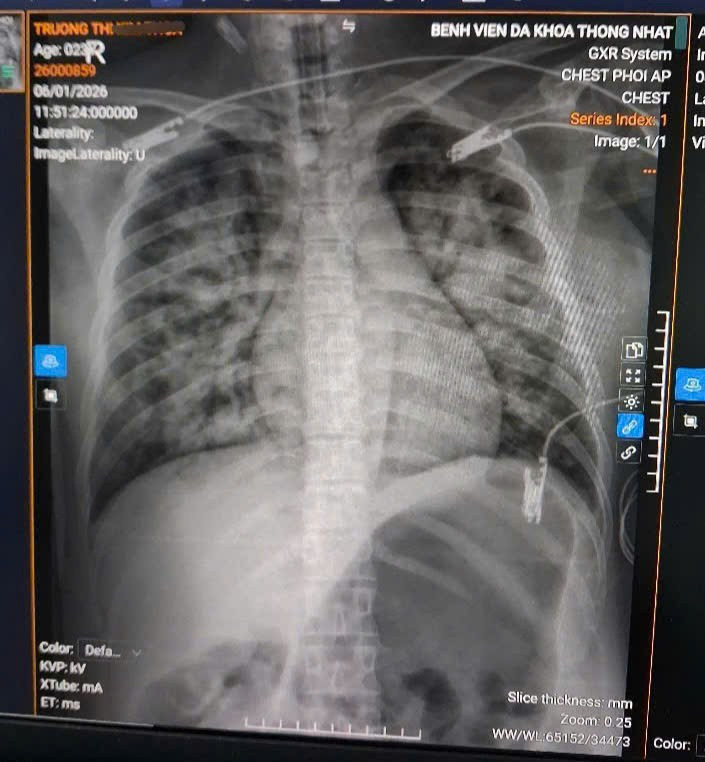

san-phu.jpg

Hình ảnh tim phổi bệnh nhân trên phim chụp - Ảnh BVCC